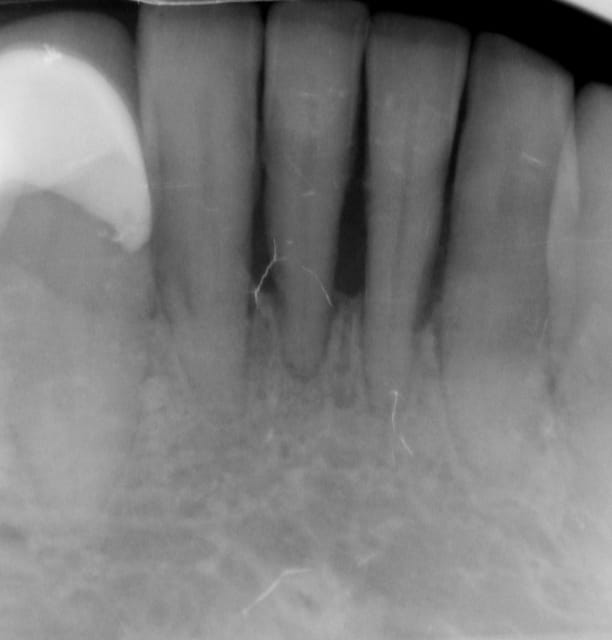

Oui tu as bien raison :-) Ci joint quelques photos en rapport avec ta question ....

20120327 154220 azpc5k - Eugenol

20120327 152704 psin9r - Eugenol

11 immidiat implantation ajhuew - Eugenol